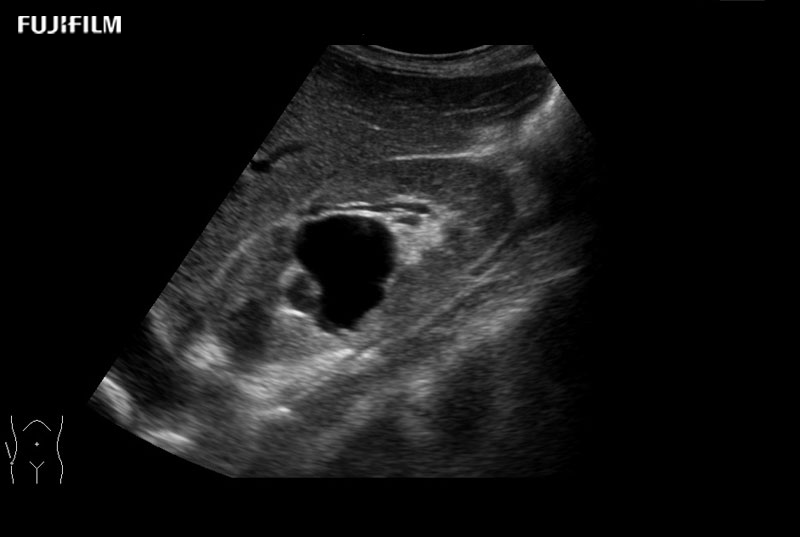

Use of trapezoid mode with a linear transducer extends the width of the field of view permitting a greater understanding of the orientation and size of the target and its surroundings.